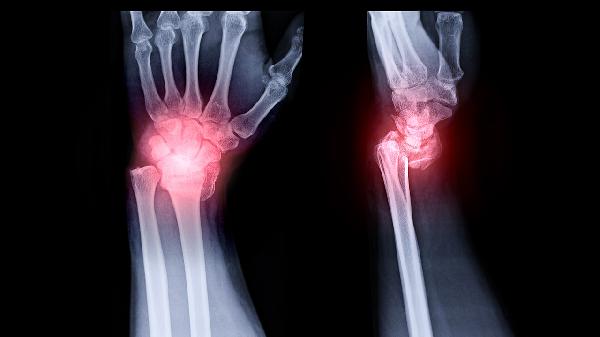

退行性关节炎患者可遵医嘱使用塞来昔布胶囊、硫酸氨基葡萄糖胶囊、双醋瑞因胶囊、玻璃酸钠注射液、盐酸氨基葡萄糖片等药物缓解症状。退行性关节炎通常与关节软骨磨损、炎症反应等因素有关,表现为关节疼痛、僵硬等症状,需结合药物与生活方式综合干预。